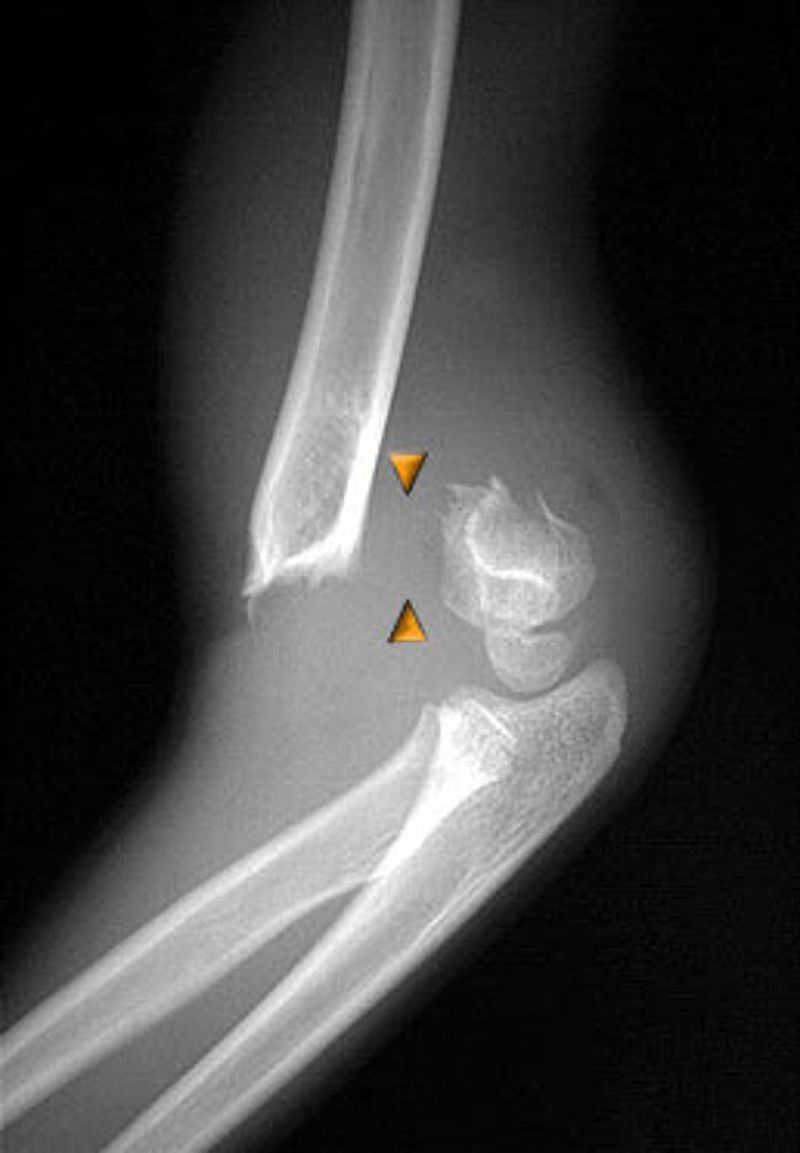

Gartland type III Fracture, A/E slab after k-wire fixation